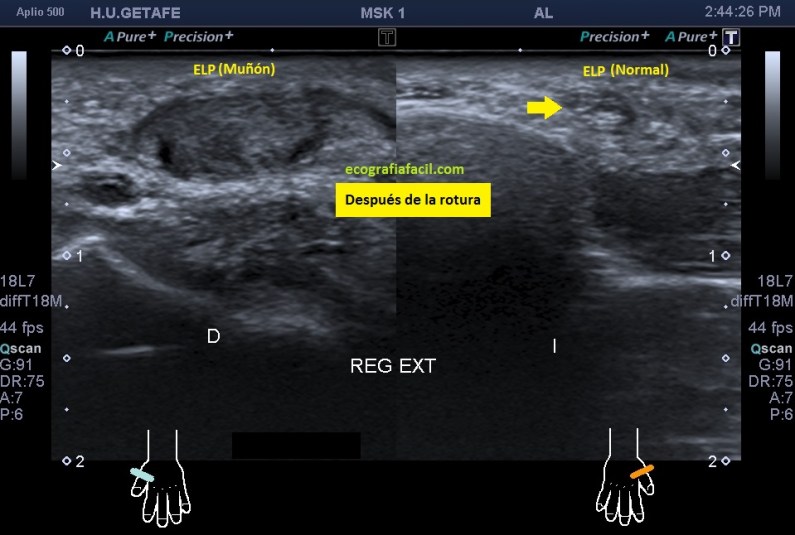

Después de la rotura, avanzando a distal, el tendón retraído, hipoecogénico, mucho más grande que su comparativo contralateral.

Esta imagen final demuestra muy claramente lo que ha pasado y como ha quedado la zona en cuestión. El tendón retraído parece continuarse hacia proximal, filiforme, hasta que llega a otro ensanchamiento hipoecogénico, en relación con el muñón proximal.